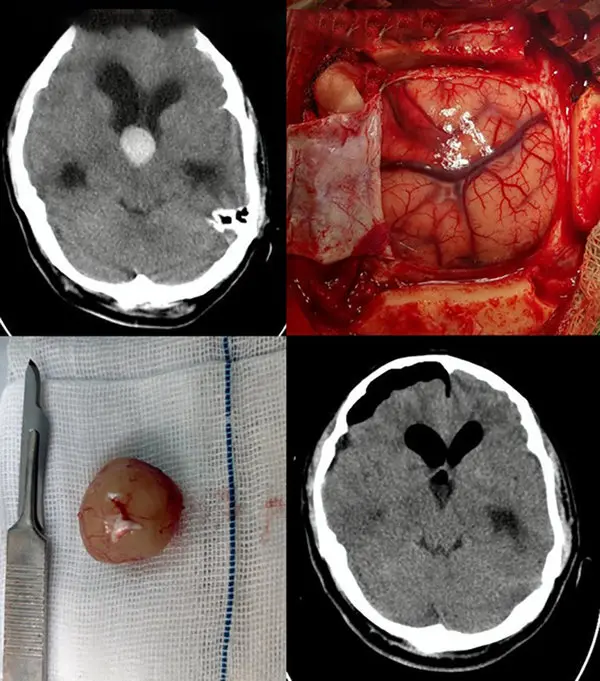

به گزارش رکنا ، رئیس بیمارستان حضرت ولیعصر (عج) لامرد از انجام عمل موفقیت آمیز خروج کیست کولوئید بطن سوم مغزی مرد 37 ساله در بیمارستان حضرت ولیعصر(عج) لامرد خبر داد.

وی با اعلام این خبر گفت: آقایی 37 ساله، نیمه شب با سردرد زیاد به این مرکز درمانی مراجعه کرد و تحت سی تی اسکن مغزی قرار گرفت که تشخیص کیست کولوئید بطن سوم مغزی برای وی محرز شد که فورا بیمار به بخش مراقبتهای قبل از عمل منتقل شد و تحت عمل جراحی قرار گرفت.

" دکتر فریبرز غفارپسند" متخصص مغز و اعصاب این مرکز در مورد جزییات این عمل سخت و نادر گفت: در روش میکروسرجری با استفاده از میکروسکوپ پیشرفته مغز و اعصاب با برداشتن استخوان جمجمه از طریق یک برش کوچک کورتیکال مغزی بطن مغزی باز می شود و سپس کیست مورد نظر آزاد و به صورت کامل از جمجمه خارج شد.

وی افزود: کیست های کولوئید بطن سوم مغزی، خوش خیم بوده ولی در مکانی بسیار خطرناک در مغز واقع شده اند. این کیست ها با بستن سوراخ های مونرو که محل تخلیه مایع مغزی نخاعی هستند، باعث هیدروسفالی و افزایش فشار مغز می شوند که در صورت عدم تشخیص و درمان به موقع منجر به مرگ مغزی می شوند.